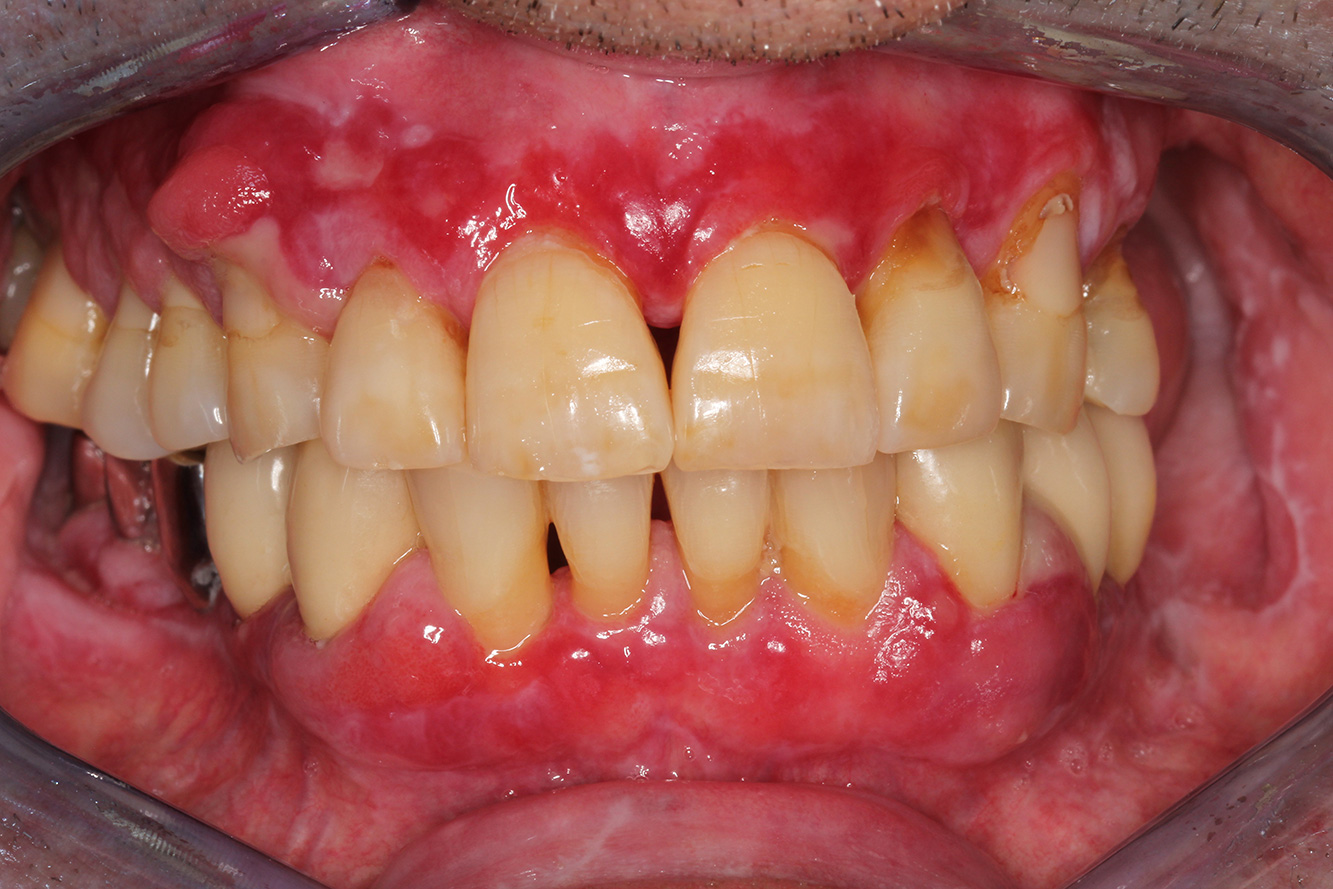

A 71-year old patient presents with having previously undergone a kidney transplant and with a history of hypertonia (high blood pressure). Due to his medical history, long-term medication with cyclosporine is required to suppress the immune system, as well as amlodipine to lower blood pressure. The patient also reports sensitive and bleeding gums. From an oral health perspective, the patient has undergone dental restoration and has eight missing teeth, pronounced gingival growth, and grade B, stage II periodontitis with active pockets and initial root caries on tooth 22. The caries risk assessment determines a moderate risk of caries (API 60). The following treatment recommendations can be determined for the prophylaxis session. more